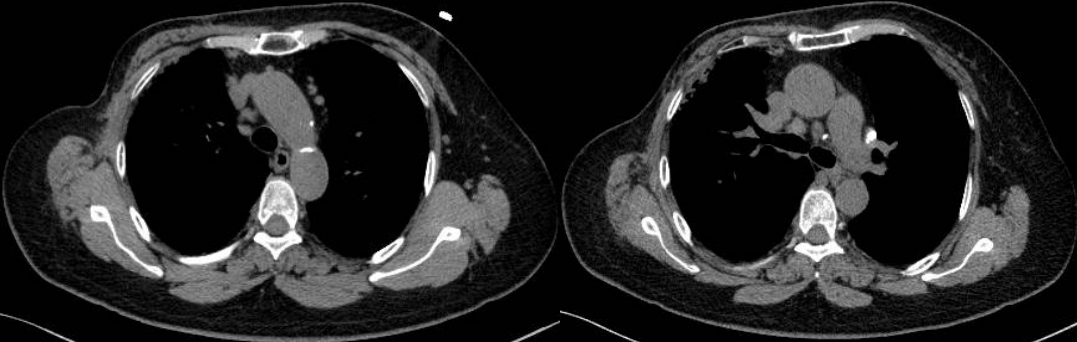

PET/CT示:雙側(cè)鎖骨上、縱隔、胸骨后、雙肺門(mén)、雙側(cè)肋骨旁、腹腔、腹膜后、盆腔及左側(cè)腹股溝見(jiàn)多枚代謝異常增高淋巴結(jié),較大者約3.4×2.1cm,SUVmax約20.7。

患者8個(gè)月后復(fù)查胸部CT示:縱隔、雙肺門(mén)淋巴結(jié)較前明顯縮小,較大者約1.4×1.1cm。

此例患者由于乳腺癌的病史,臨床初步懷疑轉(zhuǎn)移。PET/CT顯示縱隔、肺門(mén)淋巴結(jié)腫大,且呈對(duì)稱(chēng)性分布,密度均勻,邊界清晰,無(wú)明顯融合,F(xiàn)DG高攝??;此外可見(jiàn)多發(fā)腹盆部,頸部淋巴結(jié)次之,分布較散,體積及FDG攝取小于縱隔和肺門(mén)淋巴結(jié),也不是乳腺癌術(shù)后易轉(zhuǎn)移的部位。綜上考慮符合結(jié)節(jié)病表現(xiàn),最終得到病理證實(shí),患者因此避免了不必要的抗腫瘤治療。